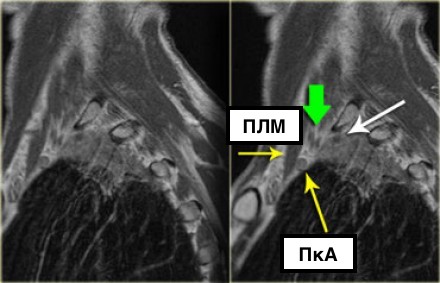

Выполнение МРТ приоритетнее в связи с лучшим мягкотканным контрастом в сравнении с КТ. |

На данном постконтрастном Т1-изображении представлена неоперабельная опухоль (T4) Панкоста. Заметна инвазия в плечевое сплетение (белая стрелка) и инвазия в подключичную артерию (а).